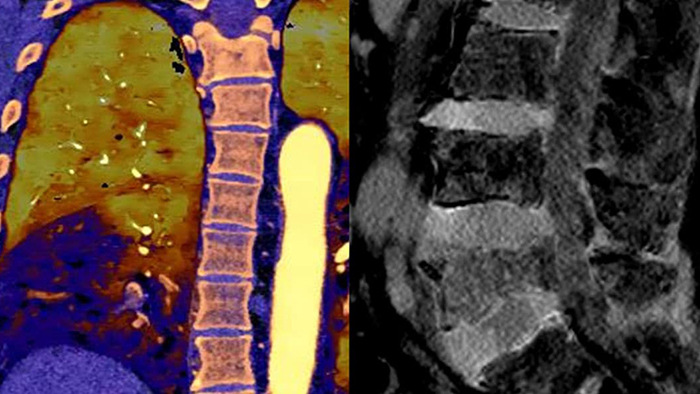

Neck mass